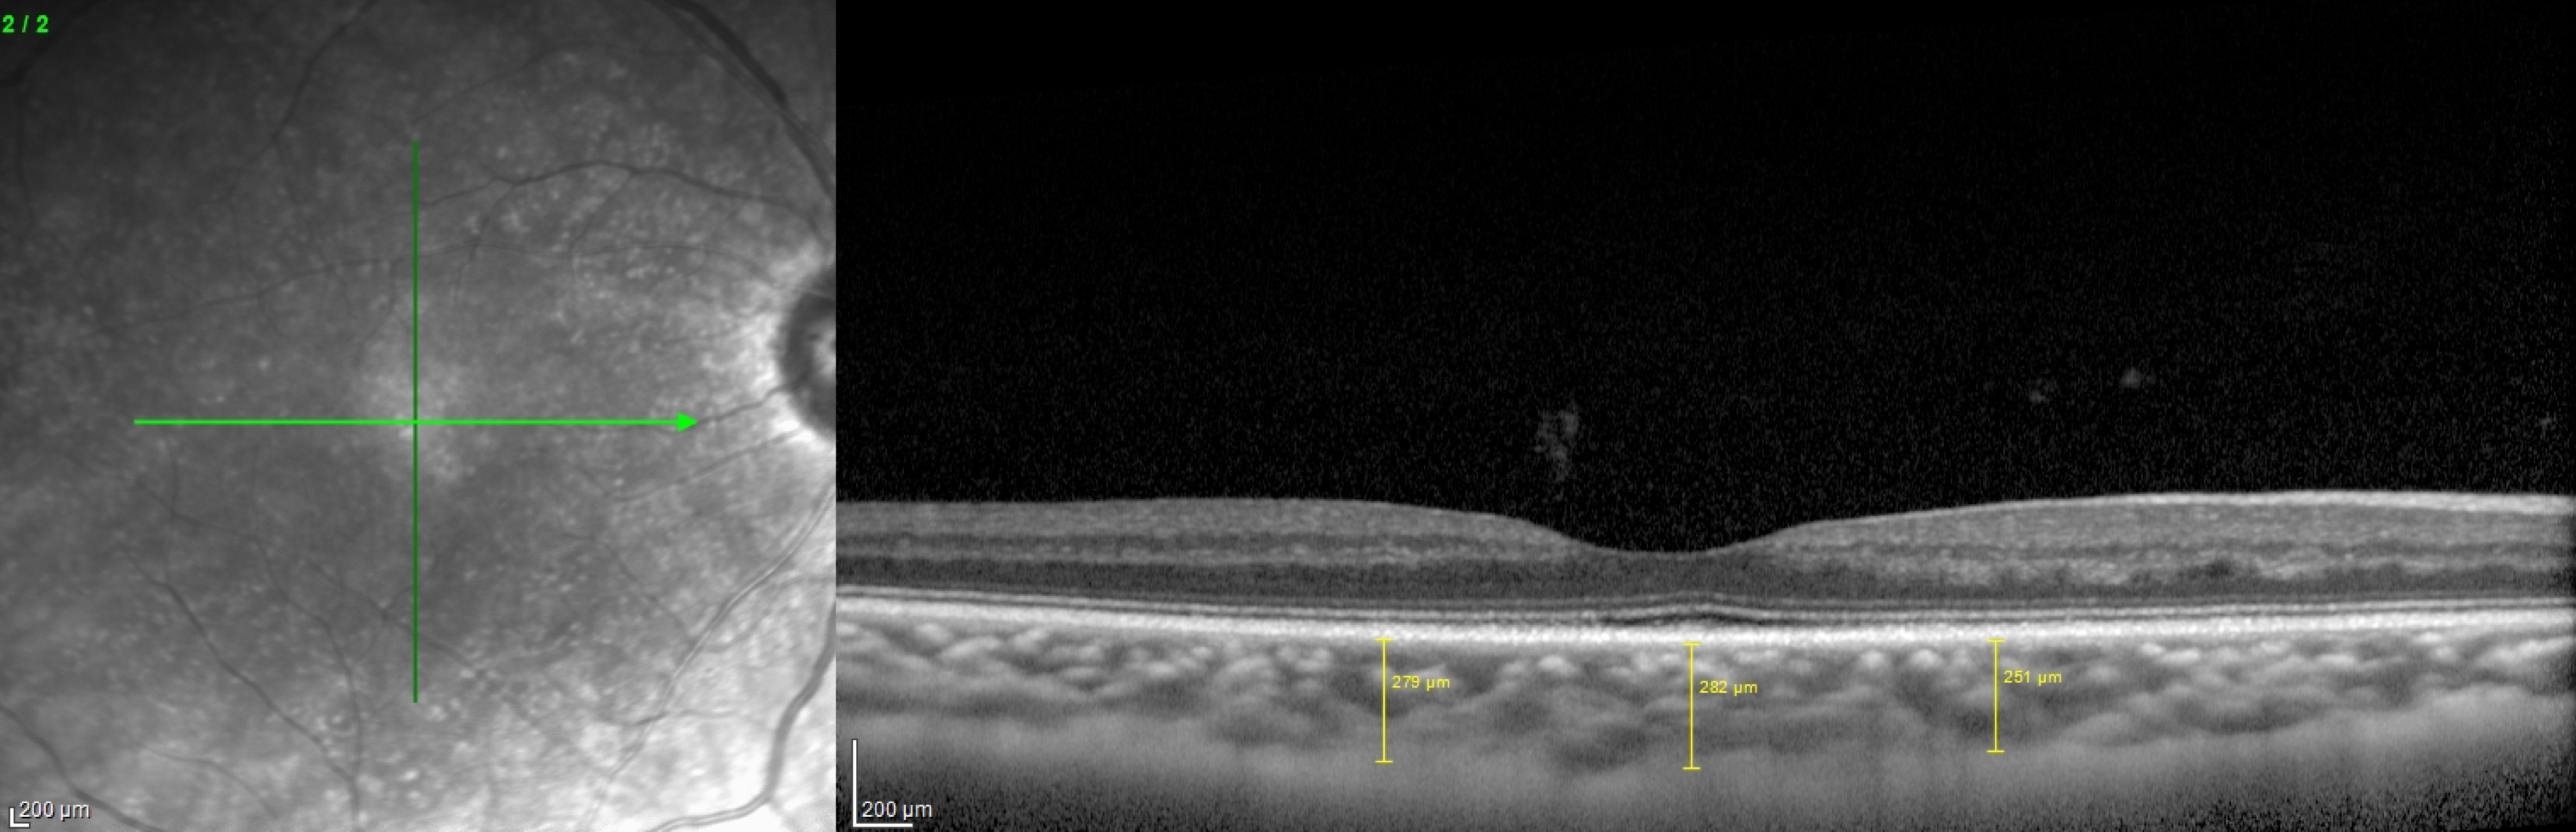

Introdução: A hemodiálise (HD), técnica substitutiva da função renal utilizada em doentes com doença renal crónica terminal (DRCT) está associada a alterações hemodinâmicas bem descritas. O estudo da resposta de tecidos altamente vascularizados como a retina e coroideia a estas alterações hemodinâmicas pode permitir melhorar o conhecimento da fisiologia da circulação ocular. O objectivo deste estudo foi avaliar as alterações, antes e após uma sessão de HD, na espessura da coroideia (espessura da coroideia) nas localizações subfoveal (SF), a 1000 μm nasal (N) e temporal (T) ao centro da fóvea bem como a espessura macular central (EMC) utilizando tomografia de coerência óptica de domínio espectral em modo enhanced-depth imaging (EDI SD-OCT). Materiais e Métodos: estudo prospectivo com 31 olhos de 17 doentes (9 mulheres) com DRCT sob HD crónica. Foram adquiridas imagens de EDI SD-OCT maculares uma hora antes e uma hora após a HD. A espessura da coroideia foi medida manualmente pelo mesmo operador e a EMC determinada automaticamente. Consideramos significância estatística p<0.05. Resultados: A espessura da coroideia nas localizações SF, N e T aumentou de 249.45±12.1 para 266.35±12.2μm (p=0.005), de 221.90±12.8 para 248.10±13.1μm (p<0.005) e de 242.23±11.7 para 271.29±26.2μm (p=0.21), respectivamente. A EMC não alterou significativamente com a HD (de 214.81±6.11 para 214.81±5.8μm, p=1.0). Conclusão: A espessura da coroideia aumentou com a HD em doentes com DRCT. A autorregulação vascular da coroideia e o shifiting de fluido e moléculas entre o sangue e interstício da coroideia podem estar envolvidos na alteração da espessura da coroideia com a HD.